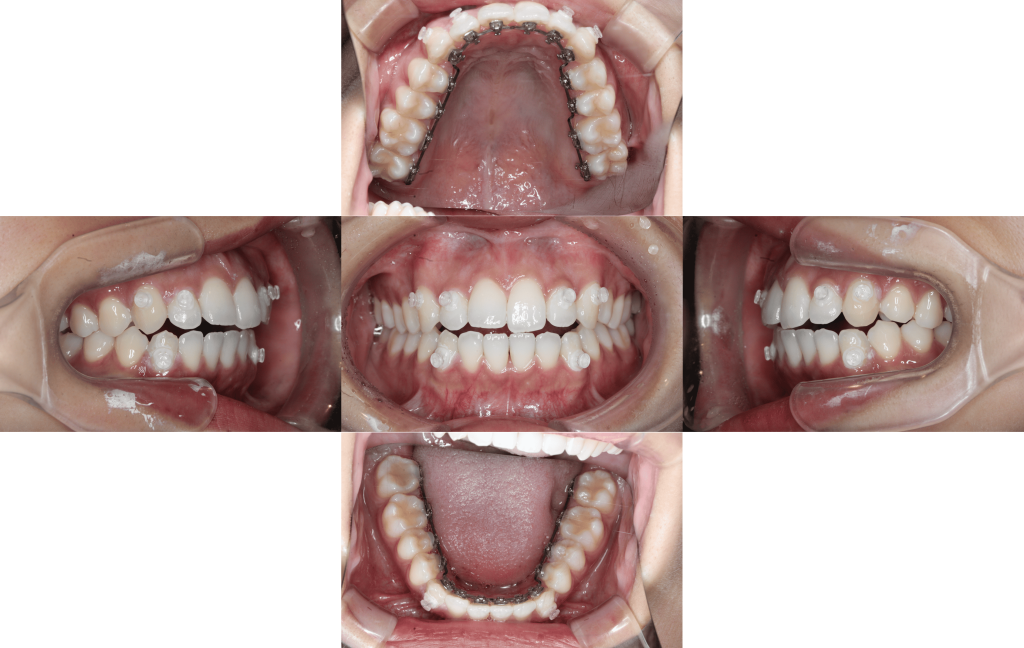

Before

初診

・上の歯のでこぼこ・1┴1曲がっている

マルチブラケット装置(裏側矯正)